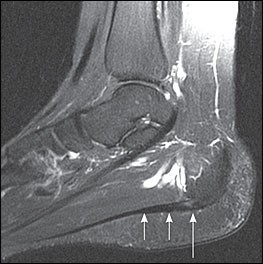

概要

足底腱膜と踵の付着部への伸張性または圧迫性の機械的負荷により微小損傷を繰り返し起こし形成される有痛性の変性病変が主体となります。そのため、長時間の立ち仕事や歩行、体重増加、靴の不適合、スポーツ(ランニングやジャンプなど)による使いすぎが主な原因と考えられます。10人に1人が生涯中に罹患し、約9割の患者は保存治療により12ヶ月以内に症状が改善すると言われています。

MRI

腱膜肥厚や変性、腱膜周囲炎や踵骨骨髄腫を認める。

超音波検査

腱膜の肥厚や低エコーで描出される変性像(右:正常/左:異常)